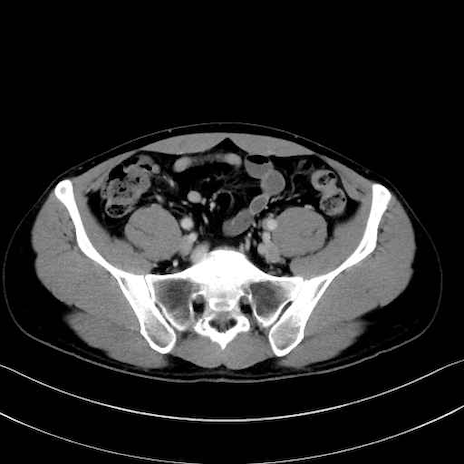

3. 殿部の筋肉(表層・中層・深層)

大殿筋 (Gluteus maximus)

中殿筋 (Gluteus medius)

小殿筋 (Gluteus minimus)